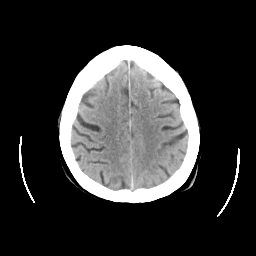

CT Study #2 -- Slice #22